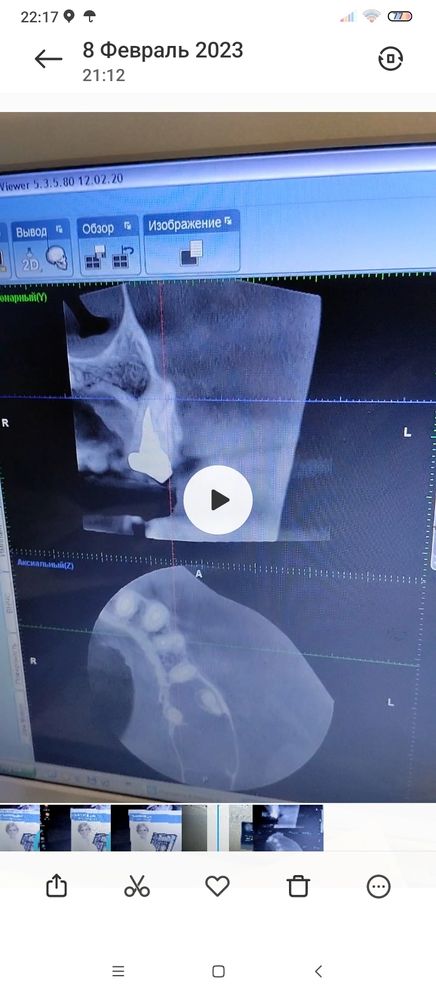

Доброго времени. После простуды начало закладывать нос, потом возникло воспаление щеки и дёсен, внешне не очень видно. при любом движении от зубов отдаётся в голову. Была температура 37,5,голова который день ватная. Есть подозрение на гайморит, но лор по телефону сказал что нужно сначала лечить зубы, потом гайморит. Сделала снимок, к зубному лечить попаду на приём только 15 го числа. Помогите расшифровать фото, тк врач к которому записалась и тот что первым смотрел снимок сказали совершенно разные вещи, один прописал антибиотик и лечение каналов одного зуба, а другой сказал что все не так плохо и назначил лечение другого зуба. И теперь я в ступоре кому верить и что делать, тк голова плывёт зубы при ходьбе ноют